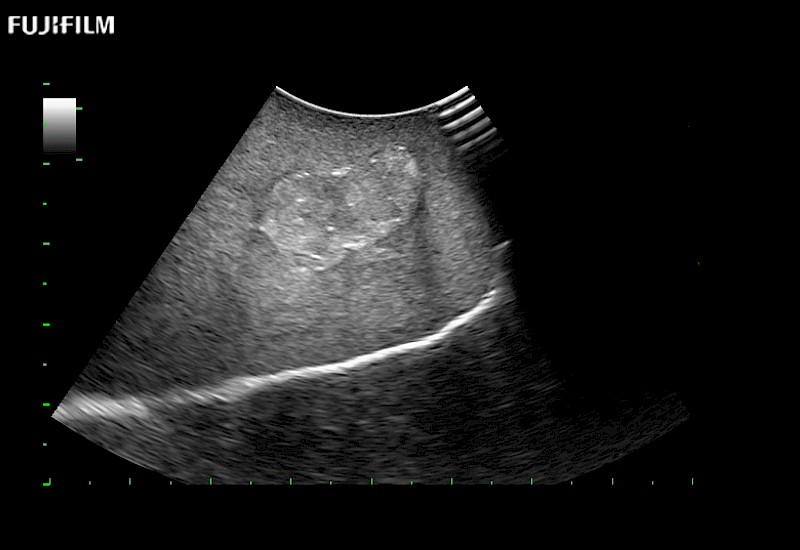

Extraordinary high-resolution digital imaging

- Instant feedback on tumor margin delineation

- Valuable information to guide tumor resections

- Instant feedback on tumor margin delineation

- Exceptional near and far-field resolution

- Instant feedback on tumor margin delineation

- Instant feedback on tumor margin delineation

- Instant feedback on tumor margin delineation

- Instant feedback on tumor margin delineation

- Valuable information to guide tumor resections

- Instant feedback on tumor margin delineation

- Valuable information to guide tumor resections

- Instant feedback on tumor margin delineation

- Valuable information to guide tumor resections

- Instant feedback on tumor margin delineation

- Valuable information to guide tumor resections

- Instant feedback on tumor margin delineation